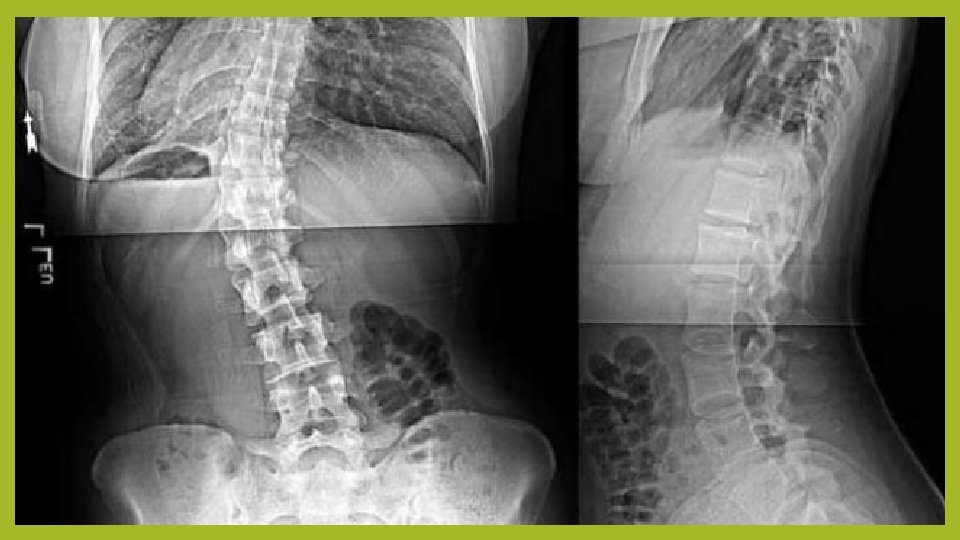

SKOLIOZE – DEFINICIJA I PODJELA - skolioza predstavlja svako iskrivljenje kralježnice gledano sprijeda ili straga u frontalnoj ravnini - može biti izražena u desnu ili lijevu stranu, a može biti i obostrana te tada nailazimo na dvije krivine - prema broju krivina, mogu biti jednostruke i višestruke - prema dijelu kralježnice koji je zahvaćen mogu biti lumbalne, torakalne i torakolumbalne

SKOLIOZE – PODJELA - točnu lokalizaciju određujemo prema vrhu samog zavoja: 1) kod torakalne skolioze vrh zavoja je između kralježaka Th 2 i Th 11 2) kod torakolumbalne skolioze vrh je na Th 12, L 1 ili disku između ta dva kralješka 3) kod lumbalne skolioze vrh je između diskova L 1/L 2 i L 4/L 5

IDIOPATSKE SKOLIOZE - izraz idiopatska znači da nema poznat uzrok - u pravilu se sve skolioze pojavljuju i napreduju tijekom razvojnog doba - nakon rotacije kralježnice javlja se „primarni zavoj”; da bi trup ostao kompenziran, tj. da bi se održao balans kralježnice, pojavljuje se i „sekundarni” ili kompenzacijski zavoj, koji se može nalaziti ispod ili iznad primarnog, a pokazuje zakrivljenost na suprotnu stranu od primarnog - najčešće se radi o desnoj torakalnoj i lijevoj lumbalnoj skoliozi

PREGLED I DIJAGNOSTIKA - obiteljska i osobna anamneza - specifične metode fizikalne pretrage (gibometrija, mjerenje duljine donjih ekstremiteta) - rendgensko snimanje kralježnice - bolesnika promotriti u stojećem stavu, promatra se horizontalni položaj ramena i zdjelice, balans trupa i položaj lopatica - test pretklona; ako postoji asimetrija ramena i lopatica, a gibusa nema, radi se samo o skoliotičnom držanju, odnosno nestrukturalnoj skoliozi